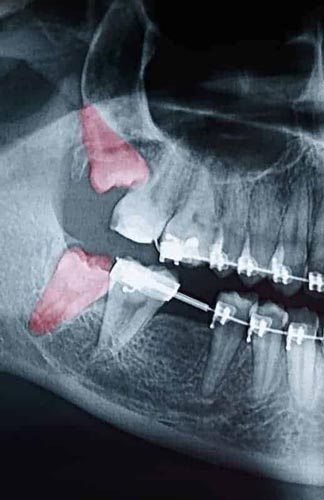

Most people’s mouths only have enough room for 28 teeth. When your wisdom teeth start to come in, that’s four additional teeth trying to cram their way in. In the majority of situations, this creates a litany of problems, including crowding, soreness, risk of infection, and the need for extraction. Since your wisdom teeth are the last teeth to erupt in through your gums, they come to the party a little late. All your other teeth have settled into their places. With x-rays and inspections, we can determine if your wisdom teeth are impacted and need to be removed. Since wisdom teeth rarely come in straight and even with the rest of your smile, we have years of experience analyzing them and extracting them at the Oral & Facial Surgery Center. Wisdom teeth can also come in sideways, causing even more issues for you if we don’t act. If you or your child is approaching the age of 18, it’s crucial to bring them in for an examination for their wisdom teeth. Call us today to schedule your appointment for a wisdom teeth analysis or extraction in the Lafayette and Opelousas area.

Though some patients may not require the removal of their wisdom teeth, most often, it’s needed to protect your overall oral health. Wisdom teeth can begin to grow sideways, only partially erupt, or even get stuck beneath the gum and bone. Known as impacted teeth, those that get stuck may resort to shifting positions as they try to find a pathway for eruption. When wisdom teeth don’t erupt through the gumline properly, they can create severe problems for the patient, including:

To evaluate the state of your wisdom teeth, we’ll first do a thorough examination and take x-rays of your mouth. This will help us determine if your wisdom teeth pose a current or future threat to your oral health. Early detection of issues results in better outcomes for our patients, so we recommend the first evaluation be completed in a patient’s mid-teenage years.